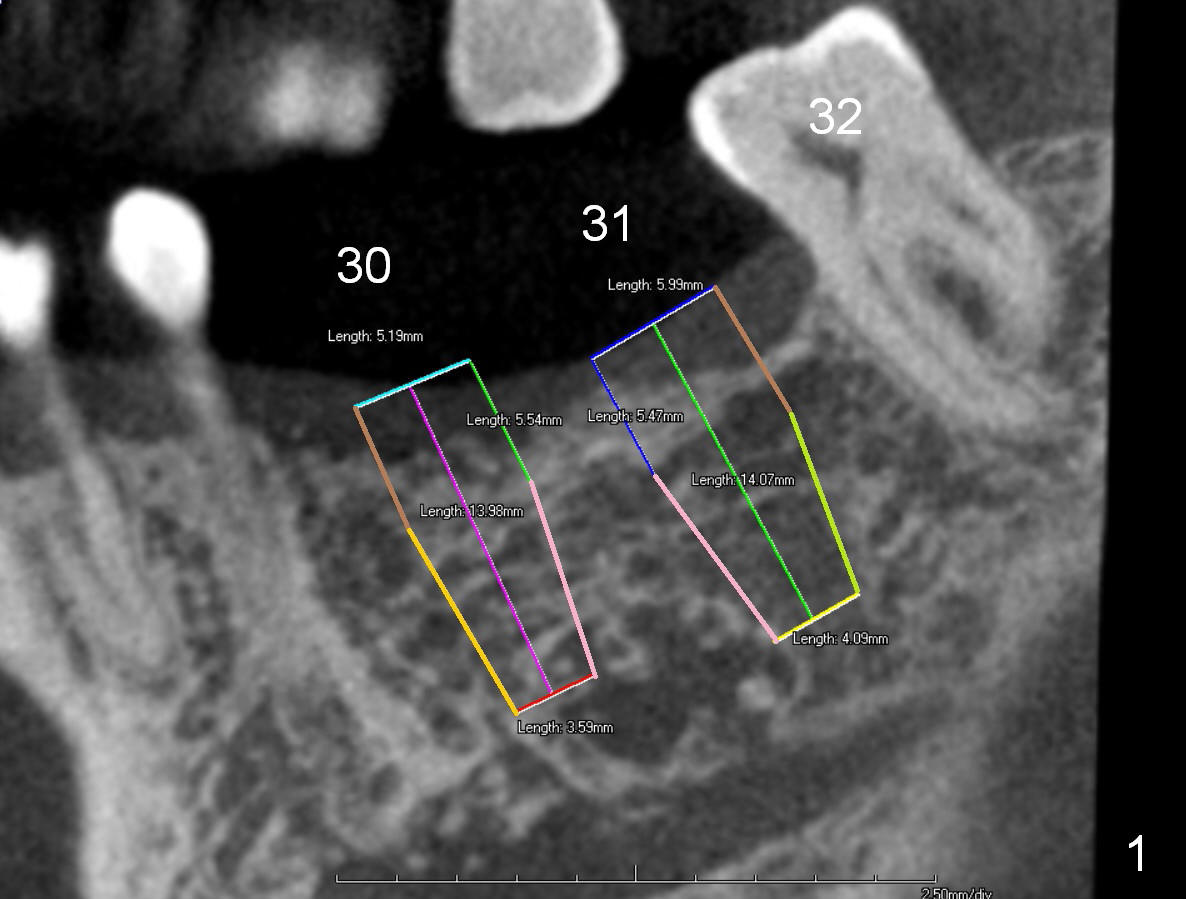

A 74-year-old man has lost the teeth #30 and 31 for a while. He is wearing a RPD and is not comfortable with it. CT analysis reveals that 5x14 and 6x14 mm implants could be placed at the site of #30 and 31, respectively (Fig.1 CT sagittal section), Fig.2,3 (coronal sections)). If implant threads are exposed, decorticate locally, place bone graft (Fig.2 red circle) and a piece of extended use collagen membrane (circling the implant, to be sutured first). If insertion torque is high for both implants, splint provisionals and minimal occlusal contact. For the best positioning, take Alginate impression when the patient returns for #8,9 implant placement.